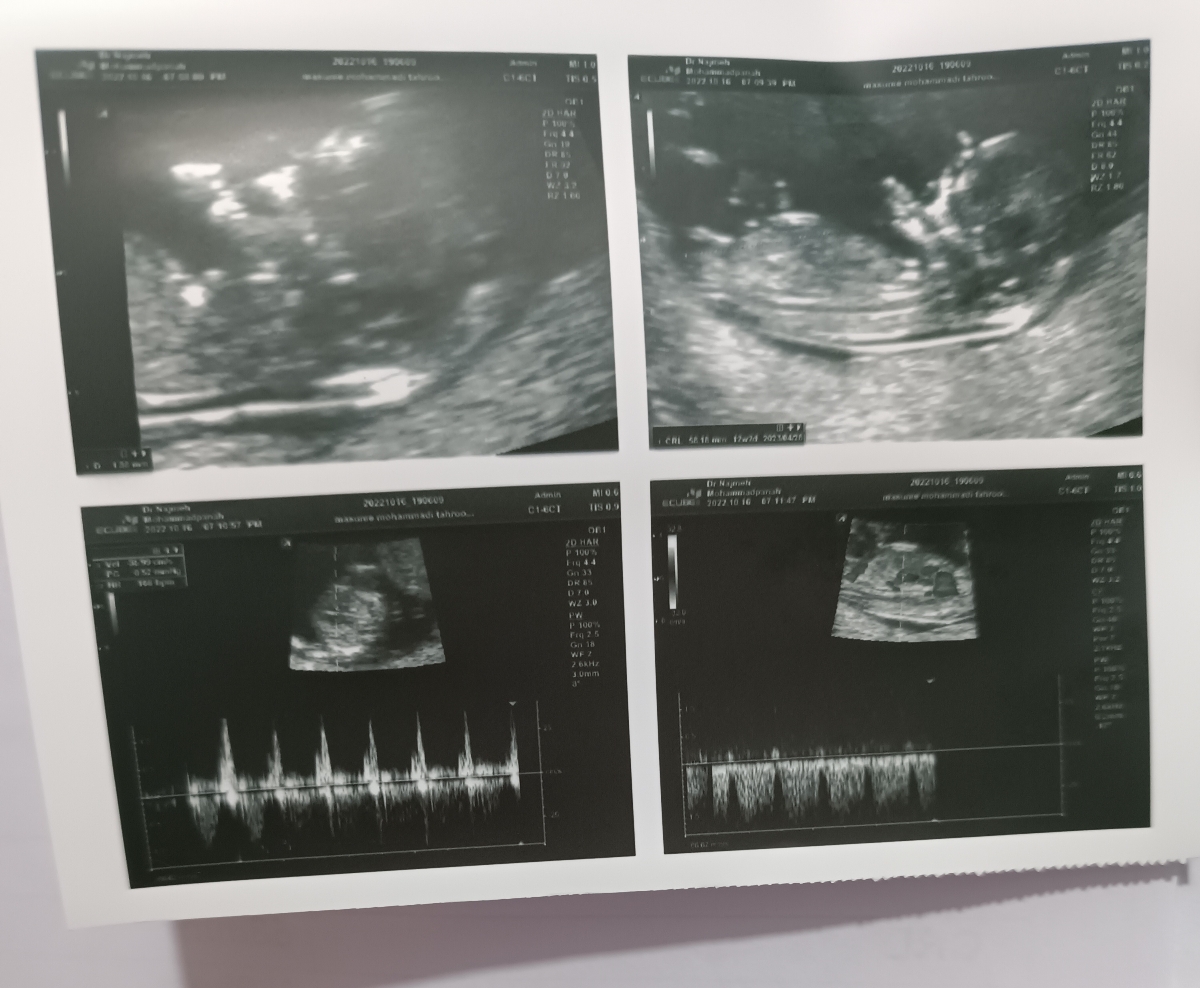

سلام من امروز رفتم سونو ان تی ، دکتر اول به دستیارش گفت عدد ان تی رو بزن ۱/۸ ولی بعدش گفت به دو هم میخوره ، بزنش ۲ . حالا سوال من اینه که آیا عدد ان تی ۲ باشه باید حتما آزمایش بدم ؟ بقیه موارد همه چی نرمال بود

عکس سونو رو میفرستم ببینید و نظرتون رو بگید لطفا

انجام آزمایش غربالگری مرحله اول ارتباطی به عدد ان تی ندارد عدد ان تی هرچه که باشد شما باید غربالگری مرحله اول را انجام دهید اما اگر عدد ان تی بالاتر از 3 بود به جای غربالگری مرحله اول یک راست باید آمنیوسنتز انجام میشد ، الان هم با فاصله زمانی کمتر از 24 ساعت حتما جهت انجام آزمایش خون غربالگری مراجعه کنید. در سونوگرافی نیز تنها نکته حائز اهمیت پایین بودن جفت است. در چنین مواردی در اغلب مواقع با افزایش سن حاملگی و بزرگ شدن رحم، دیواره های آن کشیده شده و بنابراین جفت نیز به سمت بالا کشیده می شود و مشکلساز نخواهد شد اما فعلا باتوجه به وضعیت جفت و طول سرویکس که رو به پایینراست، این موارد را رعايت کنید :